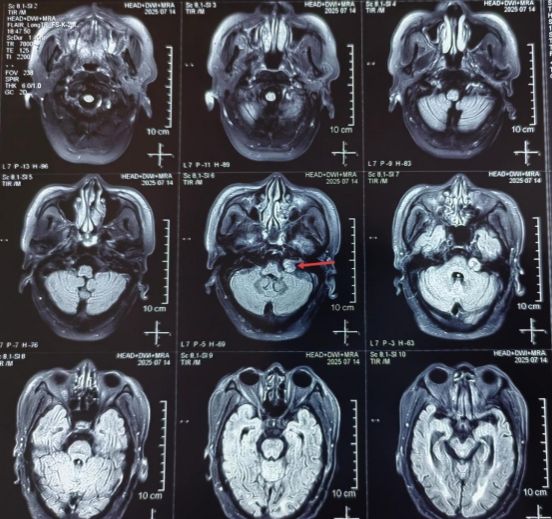

2026-02-1417岁花季少女险失明!眶尖藏肿瘤 ——我院神经外科二病区郭清保团队精准切除护视力

17岁的女孩小张(化名)近两个月来视力莫名下降、视物模糊,起初她以为是看书疲劳引发的近视,并未放在心上。直到3天前,小张突然出现头痛、恶心、食欲不振等症状,家人... -